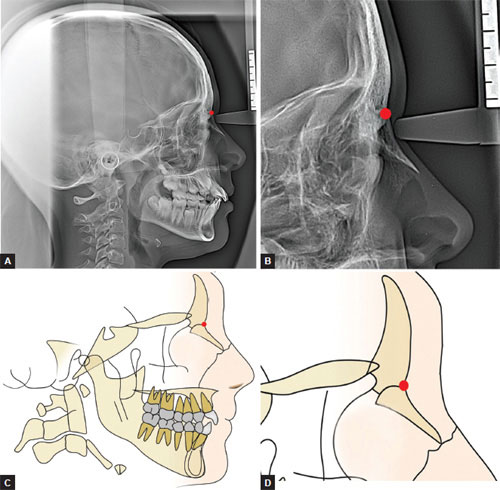

Cephalometric analysis. Measurements included (A) anterior midface ...

Nasion region (profile view). | Download Scientific Diagram